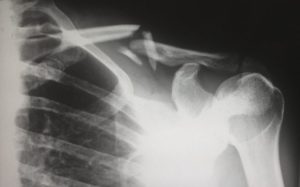

Røntgenundersøgelse